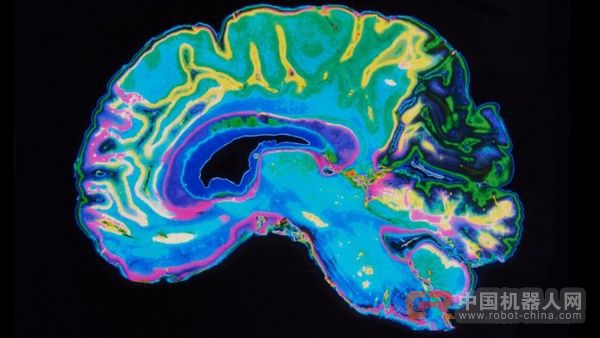

34名自愿者加入了这项研讨:17名有他杀动机,17名没有。自愿者浏览30个积极(“幸福”等)或是消极(“残暴”等)或与逝世亡相干的词(“他杀”),并斟酌了正在停止称为fMRI的脑扫描类型的寄义。

研讨人员发明,“逝世亡”,“费事”,“牵肠挂肚”,“美妙”,“赞赏”,“残暴”六个字的回应显示了两组介入者之间最年夜的差别。他们给算法供给了33名自愿者的数据。关于任何给定的单词,他们告知法式哪些神经激活形式来自哪一个组。然后,他们给算法供给了最初一位自愿者的成果,并请求算法猜测这小我属于哪一个组。机械给出谜底的精确率到达91%。在第二个试验中,迷信家们应用雷同的办法来传授一个算法来辨别那些没有测验考试过他杀的人,而这一次的精确率为94%。